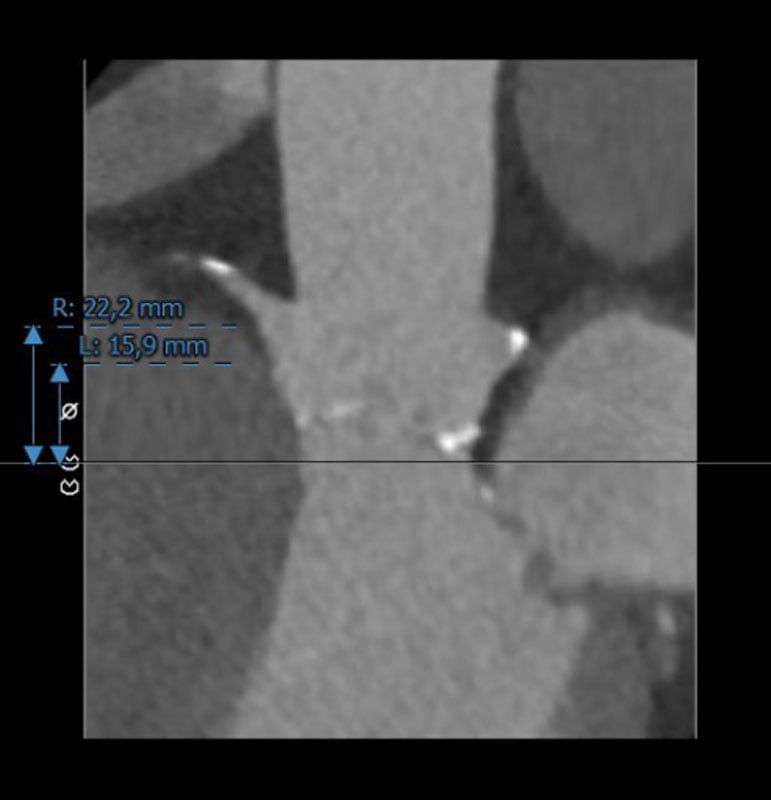

Sinus Vasalvae

LCA: 15,9 mm

RCA: 22,2 mm

Rechts

Links